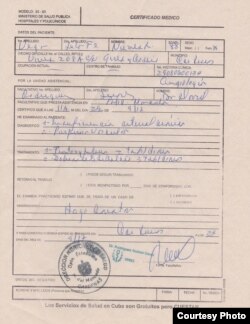

Vega de la Fe tiene edemas en los pies y padece una cardiopatía, “y se deteriora en estas circunstancias”, subrayó Alfonso Vega, quien alertó que su madre también "tiene una sepsis en los ojos, que tengo de hecho que llevarla al oculista”.